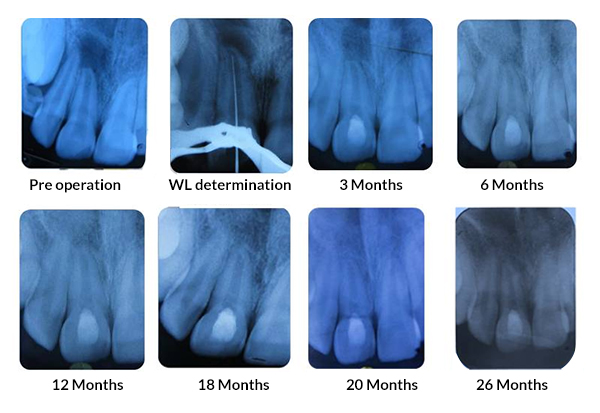

Tanisha Konai -

PRP Mediated REP in 21 with 18 months follow up

Bone healing, Apical PDL formed, Apex Closed, Calcific Bridge formed in 21.

Vitality Positive

Amanulla  -

PRF Mediated REP in 22 with 18 months Follow up

Complete Bony Healing, Calcific Bridge Formed.

PRF Mediated REP in 21 with 26 Months Follow Up

Complete Bony Healing, Apex Closed, Lateral Dentinal Wall Thickened, PDL Apically